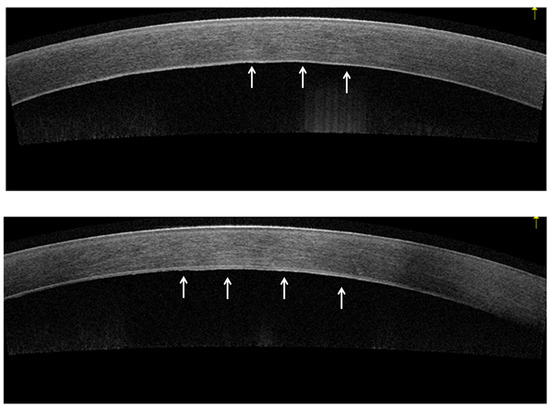

2. Anterior Segment Optical Coherence Tomography (AS-OCT)

- Augustin, V.A.; Köppe, M.K.; Son, H.S.; Meis, J.; Yildirim, T.M.; Khoramnia, R.; Auffarth, G.U. Scheimpflug Versus Optical Coherence Tomography to Detect Subclinical Corneal Edema in Fuchs Endothelial Corneal Dystrophy. Cornea 2022, 41, 1378–1385. [Google Scholar] [CrossRef]

- Huang, J.; Tepelus, T.C.; Baghdasaryan, E.; Huang, P.; Shi, Y.; Hsu, H.Y.; Sadda, S.R.; Lee, O.L. Correlation between Guttata Severity and Thickness of Descemet’s Membrane and the Central Cornea. Curr. Eye Res. 2019, 44, 849–855. [Google Scholar] [CrossRef]

- Yasukura, Y.; Oie, Y.; Kawasaki, R.; Maeda, N.; Jhanji, V.; Nishida, K. New severity grading system for Fuchs endothelial corneal dystrophy using anterior segment optical coherence tomography. Acta Ophthalmol. 2021, 99, e914–e921. [Google Scholar] [CrossRef] [PubMed]

- Shousha, M.A.; Perez, V.L.; Wang, J.; Ide, T.; Jiao, S.; Chen, Q.; Chang, V.; Buchser, N.; Dubovy, S.R.; Feuer, W.; et al. Use of ultra-high-resolution optical coherence tomography to detect in vivo characteristics of Descemet’s membrane in Fuchs’ dystrophy. Ophthalmology 2010, 117, 1220–1227. [Google Scholar] [CrossRef] [PubMed]

- Werkmeister, R.M.; Sapeta, S.; Schmidl, D.; Garhofer, G.; Schmidinger, G.; Aranha Dos Santos, V.; Aschinger, G.C.; Baumgartner, I.; Pircher, N.; Schwarzhans, F.; et al. Ultrahigh-resolution OCT imaging of the human cornea. Biomed. Opt. Express 2017, 8, 1221–1239. [Google Scholar] [CrossRef]

- Iovino, C.; Fossarello, M.; Giannaccare, G.; Pellegrini, M.; Braghiroli, M.; Demarinis, G.; Napoli, P.E. Corneal endothelium features in Fuchs’ Endothelial Corneal Dystrophy: A preliminary 3D anterior segment optical coherence tomography study. PLoS ONE 2018, 13, e0207891. [Google Scholar] [CrossRef]

- Eleiwa, T.; Elsawy, A.; Tolba, M.; Feuer, W.; Yoo, S.; Shousha, M.A. Diagnostic Performance of 3-Dimensional Thickness of the Endothelium-Descemet Complex in Fuchs’ Endothelial Cell Corneal Dystrophy. Ophthalmology 2020, 127, 874–887. [Google Scholar] [CrossRef]